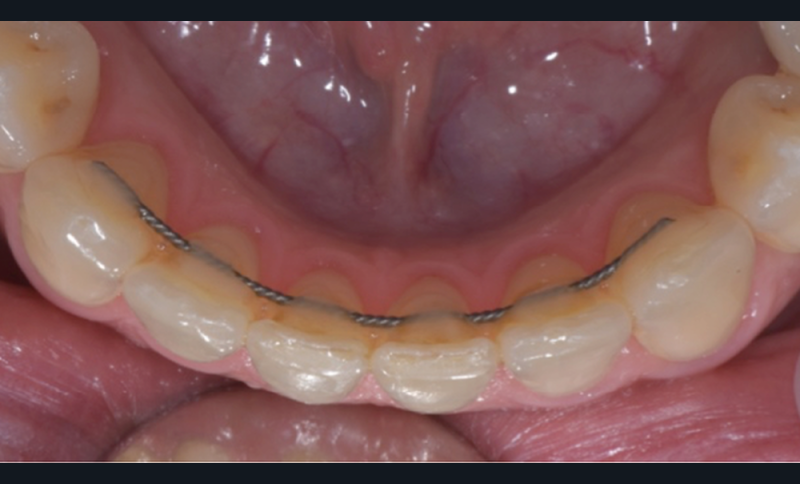

Dans le premier cas, il s’agit de plaques de nickel-titane usinées (fig. 10a-b) ou de fils de contention, pliés par un robot. Dans le deuxième cas, il s’agit de gouttières thermoformées sur des modèles (fig. 11), modifiés ou non, voire bientôt des gouttières imprimées directement.